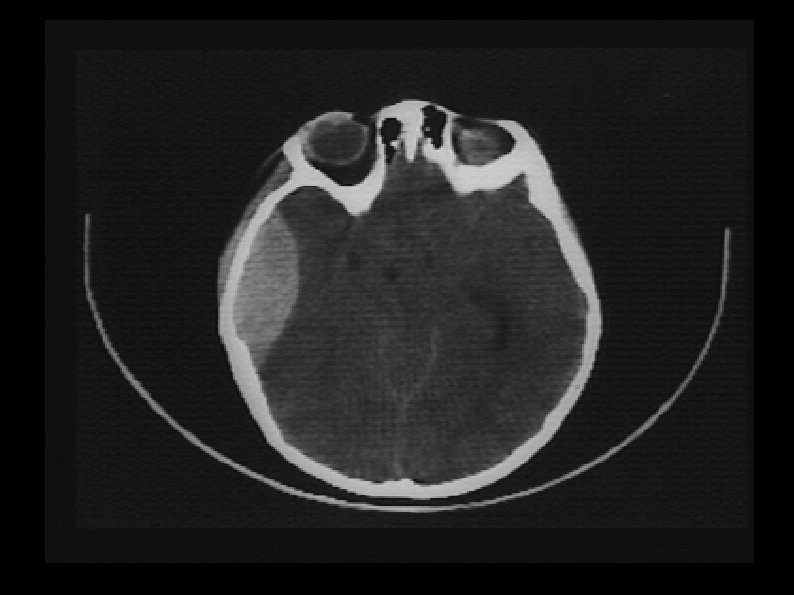

Hématome sous dural ● Diagnostic : TDM crânien, ETF souvent pris en défaut ● Évolution souvent lente, à bas bruit ● Décompensation brutale possible ● Traitement chirurgical

Hématome extra dural ● En regard d'une fracture ● Entre l'os et la dure mère ● Convexe en dedans

Hématome extra dural ● En général peu volumineux ● Traitement chirurgical